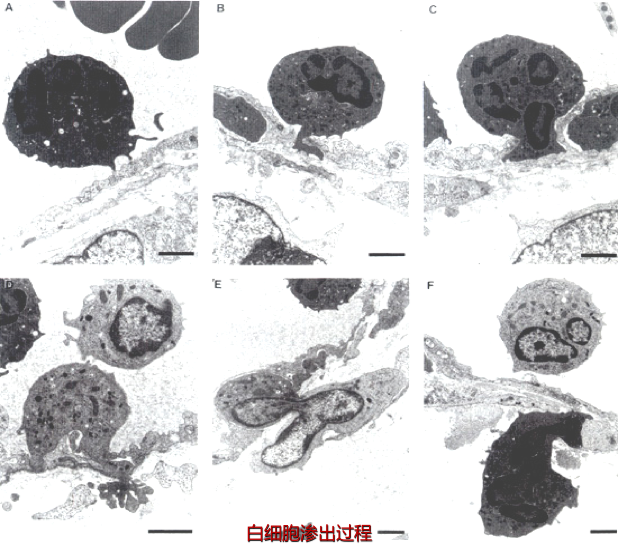

白细胞通过血管壁游出到血管外的过程称为白细胞渗出(leucocyte extravasation)。渗出的白细胞也称为炎性细胞,炎症反应的最重要功能是将白细胞输送到炎症局部。白细胞吞噬、消灭病原体,降解坏死组织和异己抗原;同时,也会通过释放化学介质、自由基和酶,介导组织损伤。因此,白细胞的渗出构成炎症反应的主要防御环节,是炎症反应最重要的特征。(白细胞的渗出机制)

白细胞的渗出及其在局部的防御作用是极为复杂的连续过程:(巨噬细胞的运动、白细胞渗出)

(1)白细胞边集和附壁:随着血管扩张、血管通透性增加和血流缓慢,白细胞进入边流,靠近血管壁,并沿内皮滚动。最后白细胞粘附于血管内皮细胞上。(下图A)

(2)白细胞粘附和游出: 目前已明确白细胞粘附和游出主要是由于其表面的粘附分子和内皮细胞受体结合引起的,化学介质和某些细胞因子可以调节这类粘附分子的表达和功能状况。这类粘附受体包括四种家族:选择素、免疫球蛋白、整合素和粘液样糖蛋白。(下图B-F)

(3)游出和趋化作用 :白细胞通过血管壁进入周围组织的过程称为游出(emigration)。粘附于内皮细胞表面的白细胞沿内皮表面缓慢移动,在内皮细胞连接处伸出伪足,整个白细胞逐渐以阿米巴样运动方式从内皮细胞缝隙游出,到达内皮细胞和基底膜之间,最终穿过基底膜到血管外(下图B-F)。中性粒细胞、单核细胞、淋巴细胞、嗜酸粒细胞和嗜碱粒细胞都是以此种阿米巴样运动方式主动游出的。